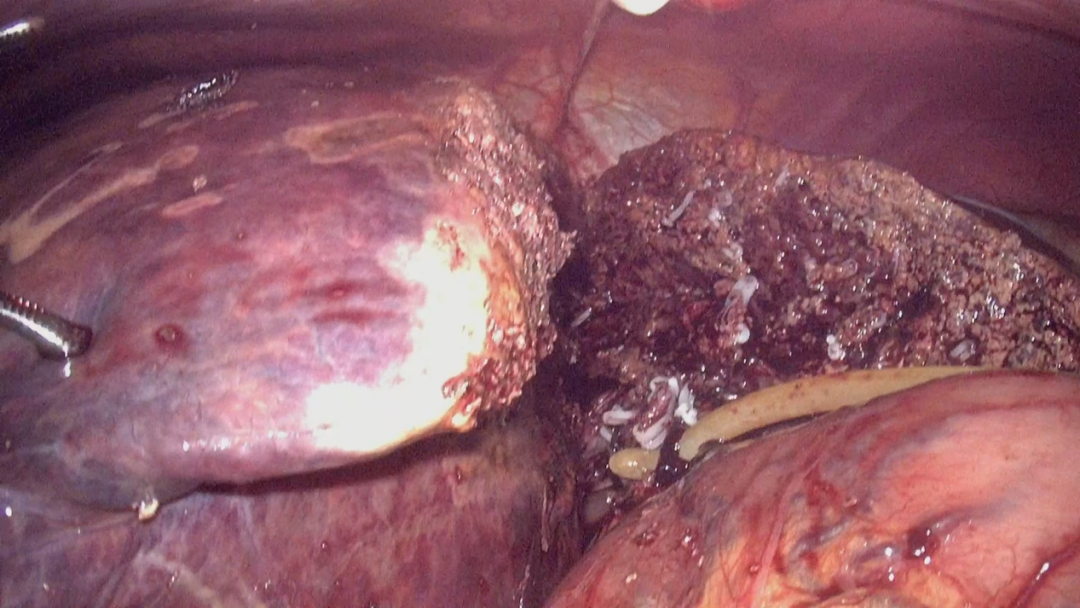

6月10日,在丁金火的周密規(guī)劃和指導下,由洪波、曾廣源、鄧高旺手術(shù)團隊及麻醉醫(yī)生、手術(shù)護士等全力配合協(xié)作,為小黃實施了術(shù)中超聲引導腹腔鏡前入路解剖性右半肝切除術(shù)。術(shù)中探查情況與術(shù)前評估基本一致,手術(shù)歷時約8個小時,出血僅100毫升。采用前入路,超聲引導下精準處理右肝流入血管后,依缺血分界離斷肝實質(zhì),不擠壓翻動腫瘤,降低癌細胞血行播散幾率,切除的腫瘤包膜完整無撕裂,重約3公斤,病理證實為中分化肝細胞癌。

術(shù)中